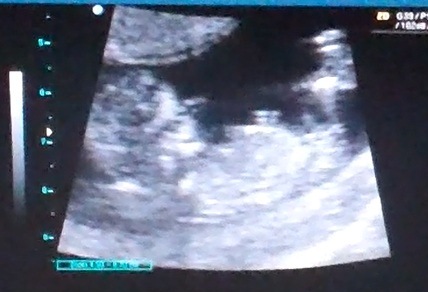

Okay I've been going through the video and pausing. . how does the nub look here?Attachment 6347

I would say it looks girly here.

Mae, it is tricky. But I'd say girl kinda looks parallel to the spine to me. Hope u get ur desired gender xx good lick